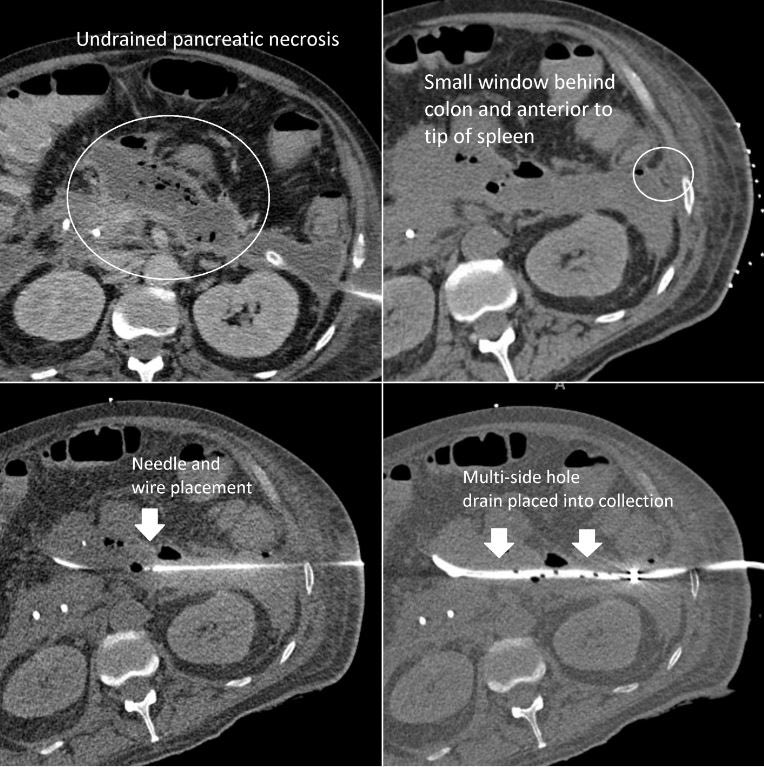

Even “simple” image-guided procedures can have huge impacts on patient care. Here, an undrained component of pancreatic necrosis was causing persistent fevers & elevated white count. #IRad used a small opening behind the colon but anterior to spleen to place a drain.